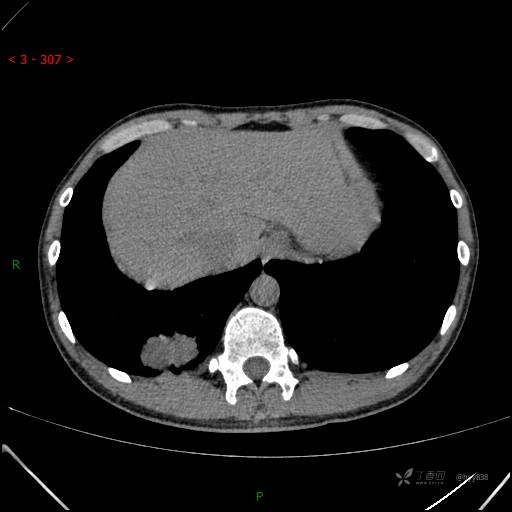

静脉期